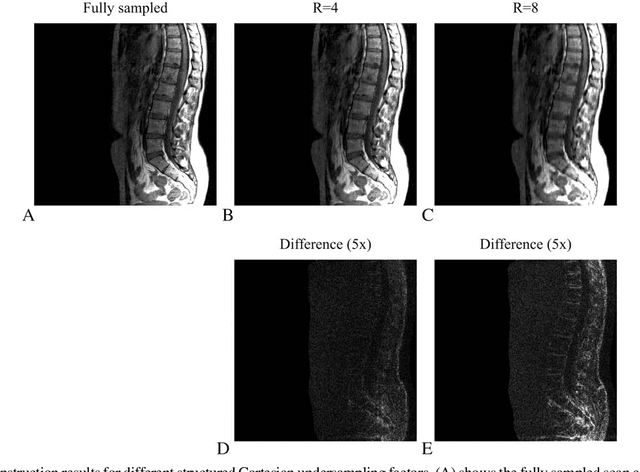

Abstract:Purpose: Design of a preconditioner for fast and efficient parallel imaging and compressed sensing reconstructions. Theory: Parallel imaging and compressed sensing reconstructions become time consuming when the problem size or the number of coils is large, due to the large linear system of equations that has to be solved in l_1 and l_2-norm based reconstruction algorithms. Such linear systems can be solved efficiently using effective preconditioning techniques. Methods: In this paper we construct such a preconditioner by approximating the system matrix of the linear system, which comprises the data fidelity and includes total variation and wavelet regularization, by a matrix with the assumption that is a block circulant matrix with circulant blocks. Due to its circulant structure, the preconditioner can be constructed quickly and its inverse can be evaluated fast using only two fast Fourier transformations. We test the performance of the preconditioner for the conjugate gradient method as the linear solver, integrated into the Split Bregman algorithm. Results: The designed circulant preconditioner reduces the number of iterations required in the conjugate gradient method by almost a factor of~5. The speed up results in a total acceleration factor of approximately 2.5 for the entire reconstruction algorithm when implemented in MATLAB, while the initialization time of the preconditioner is negligible. Conclusion: The proposed preconditioner reduces the reconstruction time for parallel imaging and compressed sensing in a Split Bregman implementation and can easily handle large systems since it is Fourier-based, allowing for efficient computations. Key words: preconditioning; compressed sensing; Split Bregman; parallel imaging